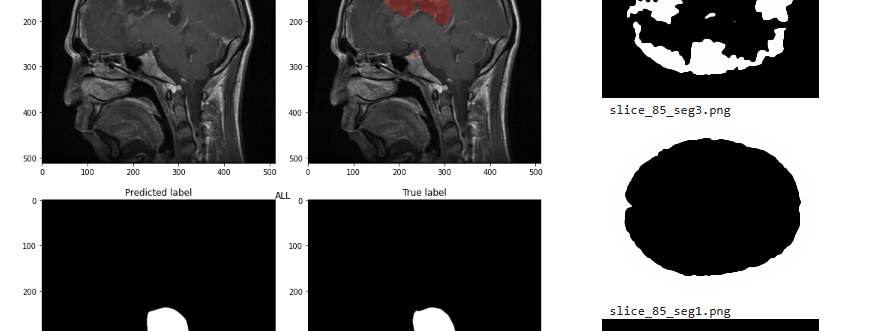

MSc Computer Graphics, Vision and Imaging

Graduated with First Class with Distinction. Overall of 76.6/100.

Modules: Final project(69/100), Machine Learning for Visual Computing(92/100), Machine Vision(61.16/100), Robot Vision and Navigation(84.01/100), Information Processing in Medical Imaging(82/100), Acquisition and Processing of 3D Geometry(90.5/100), Computational Modelling for Biomedical Imaging(66.05/100), Virtual Environments(78.2/100), Computer Graphics(89.29/100).